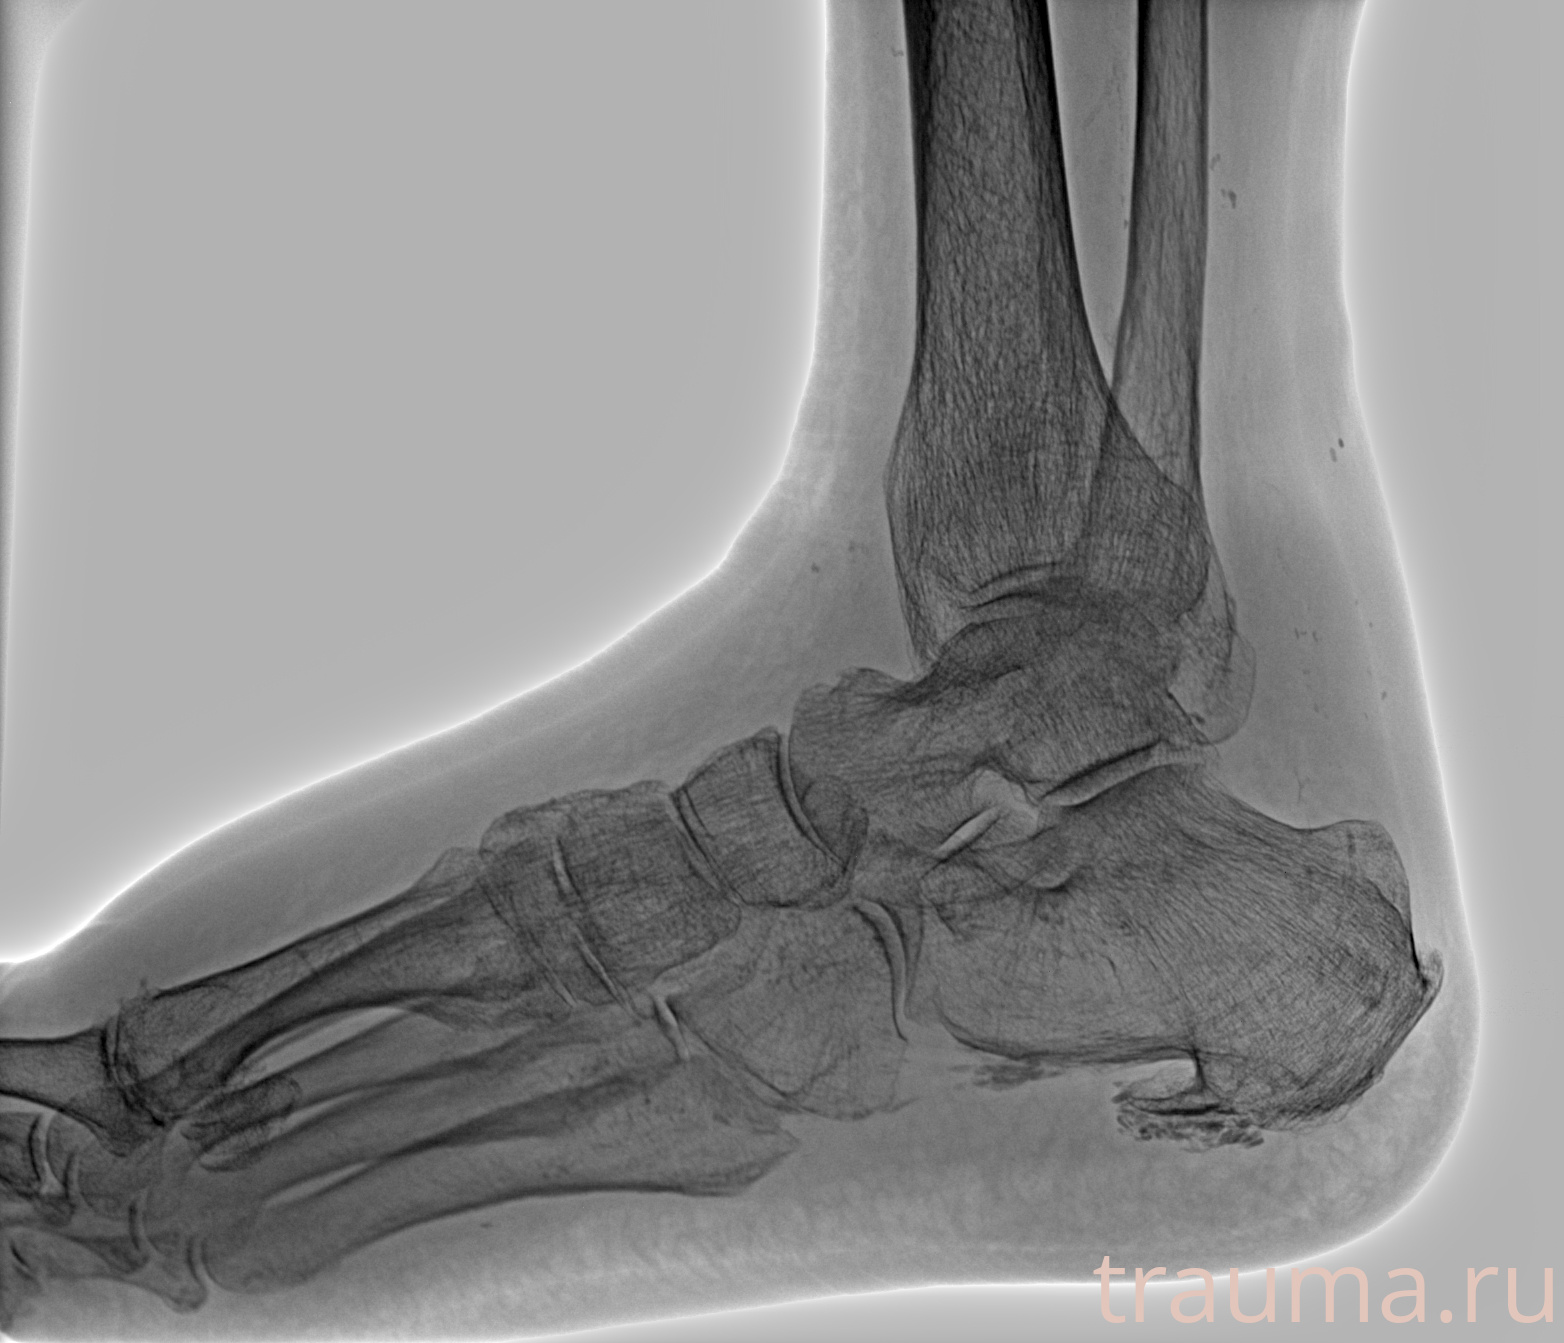

Рентген на дому: по вашему адресу приезжает врач-рентгенолог, травматолог-ортопед с мобильным рентгеновским аппаратом, проводит диагностику травмы или заболевания, делает необходимые рентгенограммы, дает рекомендации по дальнейшему лечению. Получить качественные снимки в домашних условиях возможно благодаря уникальной методике, разработанной МосРентген Центром для института  Склифосовского